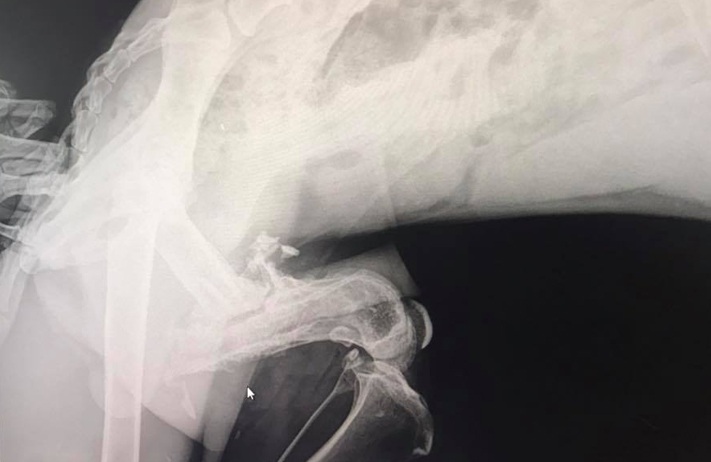

Hopper was found on the streets with a broken leg. The break was badly infected and so severe that the leg could not be saved. This poor boy is absolutely terrified. More info to come.